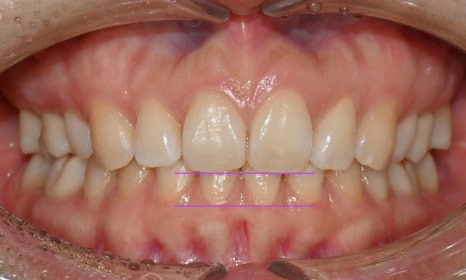

과개교합 치료 전후 사진 비교

총 3달 정도의 치료기간 동안 오른쪽 틀어진 앞니가 가지런하게 배열되었고 치아사이 공간도 타이트하게 닫을 수 있었습니다. 또한 위아래 앞니가 서로 세게 닿지 않도록 위 앞니를 위로 살짝 올려주어 과개교합을 개선하였습니다.

과개교합의 경우 일반 교정장치로 부분교정하기에는 쉽지 않은 치료과정이나, 인비절라인의 경우 부분교정으로도 어느 정도의 과개교합의 개선은 충분히 가능합니다. 치료 마무리 후 송곳니까지 고정식 유지장치를 붙이고 가철식 유지장치를 제작하여 다시 틀어지거나 벌어지지 않도록 하였습니다.